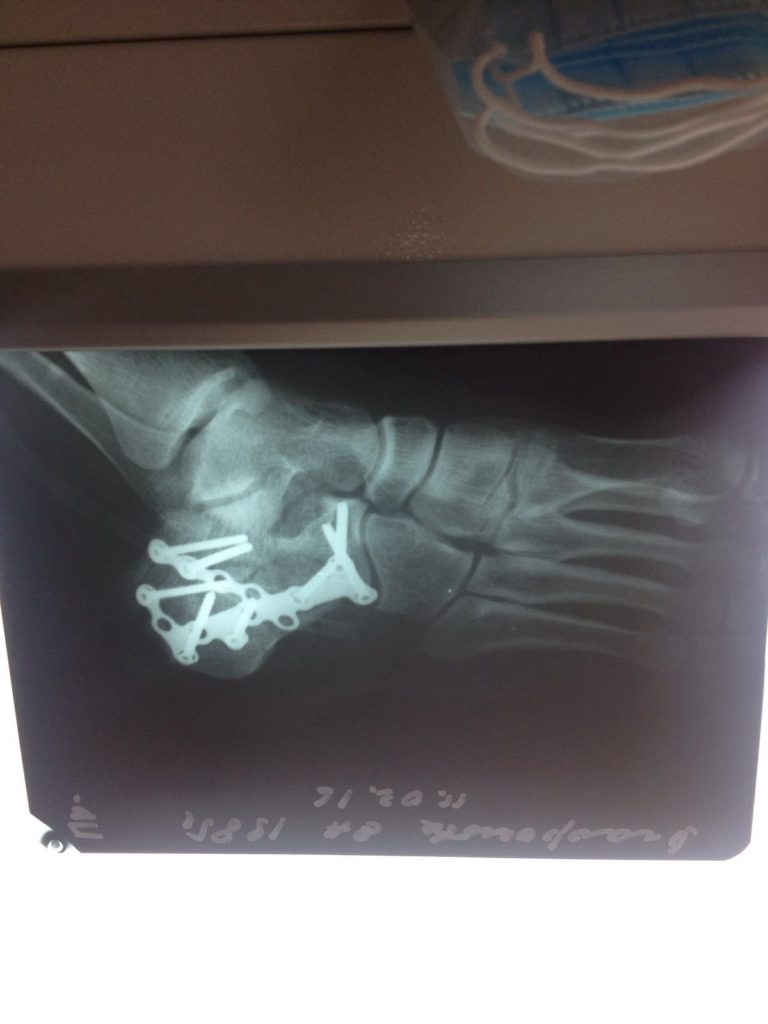

Операция – открытая репозиция, остеосинтез пяточной кости пластиной с костной ксенопластикой материалом «Остеоматрикс». На контрольных снимках в три месяца имеется консолидация перелома, миграции фиксатора нет, имеется остеоинтеграция ксенопластического материала.

Отдаленные результаты через 3 (три) месяца: